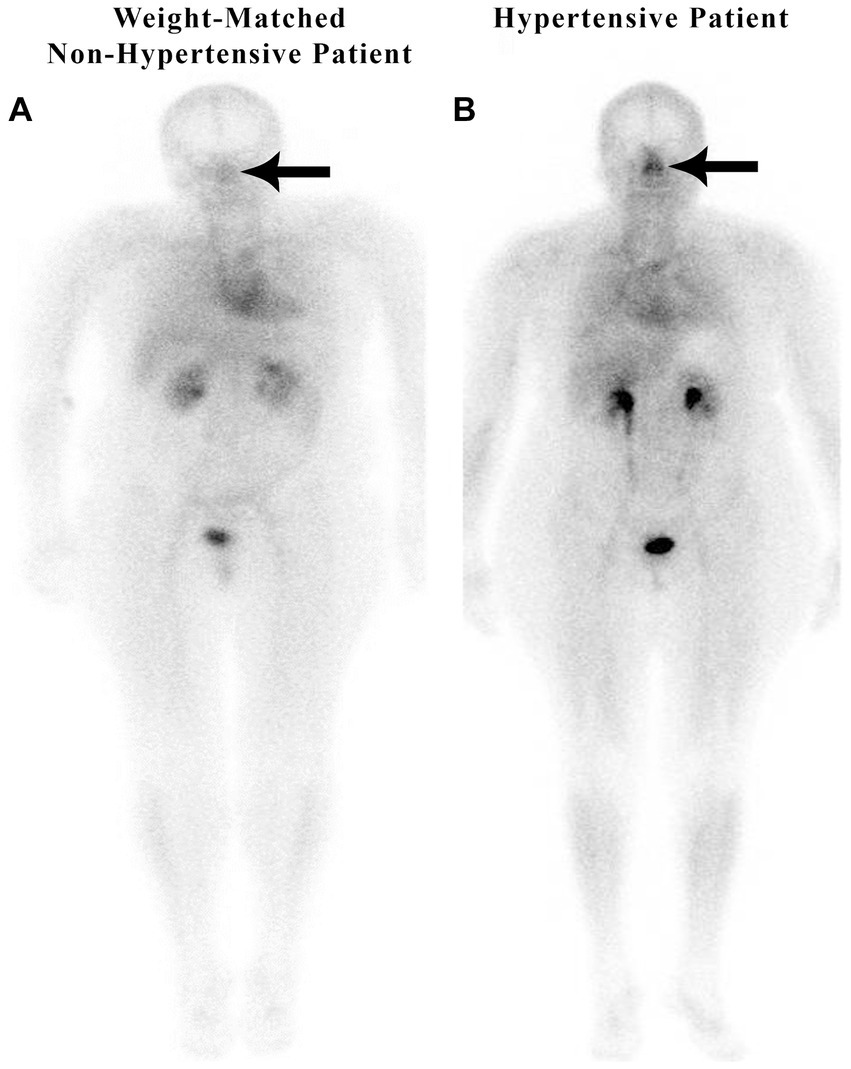

In a retrospective study of 200 patients referred for a routine bone scan, the authors observed that hypertensive patients have significant nasal blood pooling, i.e., increased nasal turbinate vasodilation, as compared to patients without hypertension (25). This increased nasal vasodilation in patients with hypertension is illustrated in Figure 1. The methodology used for obtaining the nuclear scan and the whole-body blood pool imaging is described in the following section.

Figure 1

Weight-matched, non-hypertensive (A) vs. hypertensive patient (B), both with normal BMIs.

9 Measurement of nose/heart ratios

Nose/heart ratios were determined by placing a square region of interest box over the area of the nose on the nuclear scan. The activity in the maximum pixel was determined in each box, and a ratio of the maximum pixel in the nose was divided by the maximum pixel in the heart. Using the maximum pixel activity is very similar in technique to analyzing the maximum standard uptake value (MaxSUV) as determined in PET imaging for monitoring cancer metabolism. The use of a box and maximum pixel activity decreases the subjectivity incurred with drawing an outline around the whole organ. In our retrospective study of 200 patients, those patients with hypertension had an average nose-to-heart max ratio of 0.93 versus 0.85 in non-hypertensive patients (p = 0.0123 using the Wilcoxon rank-sum test) (25). Figure 1 demonstrates a normal-weight non-hypertensive control subject (A) compared to a normal-weight hypertensive patient with increased nasal pooling (B).

Both non-hypertensive patients in Figures 1, 2 have very minimal blood activity in their nasal turbinates while both patients with hypertension have very significant activity in the nasal turbinate region. These whole-body blood pool imaging studies have provided insights to the investigators which have led to their proposal of a working hypothesis described in this paper regarding a new causation paradigm for essential hypertension. Confirmation of these findings will be important. Potential methods to confirm these findings will be addressed in section 19.